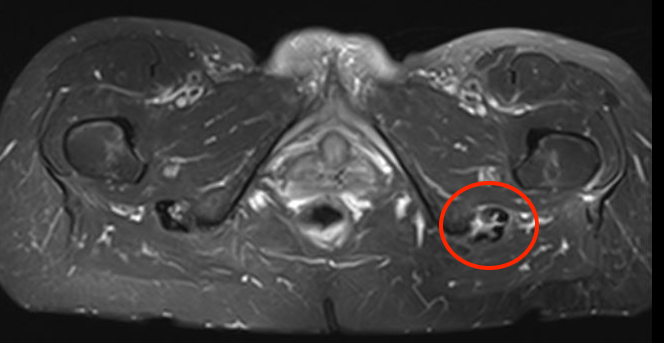

MRI

Peritendinous edema / low grade partial tears / tendinopathy

High grade partial tears